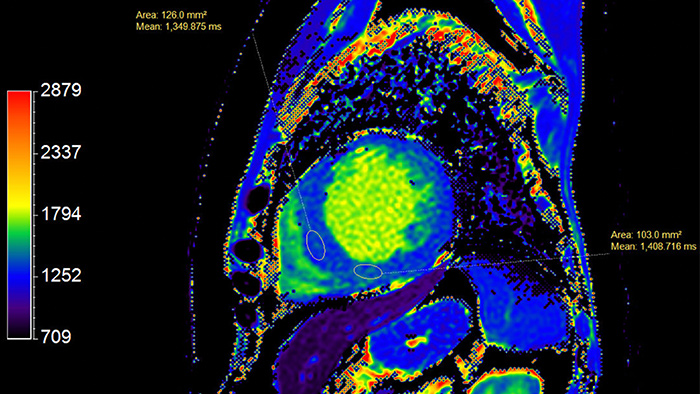

T1-картирование активно используется в диагностике инфаркта миокарда наряду с LGE. Известно, что ишемия приводит к развитию внутриклеточного отека, который, как было сказано ранее, вызывает рост времени T1 (для воды этот параметр может достигать вплоть до 5 с, в то время как типичное значение T1 в миокарде - 1-1.5 с). Инфаркт миокарда в хронической стадии (или постинфарктный кардиосклероз- ПИКС) сопровождается повышенным отложением коллагена в миокарде и образованием фиброзной рубцовой ткани, что характеризуется ростом T1.Таким образом, повышенные значения T1 (рис. 8) и ECV наблюдаются как при хронической, так и острой форме заболевания, и могут использоваться в качестве их биомаркеров. При этом рост значений более выражен при остром инфаркте миокарда, что позволяет дифференцировать данные заболевания.

В случае T1-картирования с введением контраста, на получаемых картах зоны ПИКС выделяются на фоне здорового миокарда за счет повышенного накопления в них контрастного агента, который сокращает время T1. На рис. 9 видны области пониженного значения T1, соответствующие фиброзу в результате инфаркта. Слева - рубцовые изменения по нижней стенке левого желудочка, справа - рубцовые изменения в 7, 8 и частично 9 сегментах (согласно разработанной Американской кардиологической ассоциацией 17-сегментной модели сердца [19].